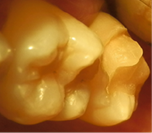

En 2013 concurre paciente de sexo femenino de 37 años de edad a la Clínica Integrada II UdelaR por caries profunda en pieza 37 (Fig. 2a). Se diagnostica CPPA ya que solo el test de fresado da positivo. Se planifica eliminación total de caries de paredes laterales con aislación absoluta. Se observa último test colorimétrico con rojo ácido 52 en propilenglicol (Detector, Pharma Dent, Uruguay) dejando fina capa de dentina infectada en pared axial (Fig. 2b) la cual se protege con mezcla de hidróxido de calcio (Ca(OH)2) puro con suero fisiológico y luego encima Ca(OH)2 fraguable (Life, Kerr, USA) (Fig. 2c). Se sella con ionómero vítreo (Gold Label Luting & Lining Cement, Tokyo, Japan).